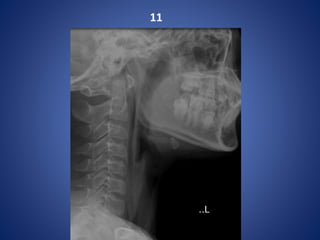

11

Extended Pneumomediastinum

Retrophyrangeal abscess Extended Pneumomediastinum